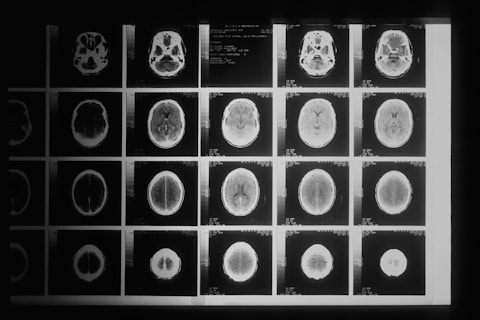

Eine Abklärung durch den Neurologen ist unbedingt notwendig, da die Behandlung je nach Form variiert. Häufig werden dafür neurologische Tests, Bildgebung (MRT, DaTSCAN) und Beobachtungen über längere Zeiträume kombiniert.